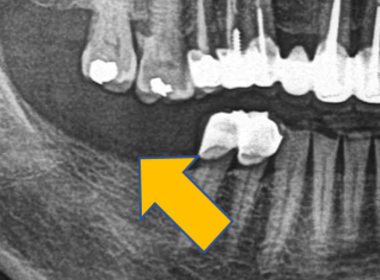

| 0709 #36#37 左下第一第二大臼齒 |

![]() |